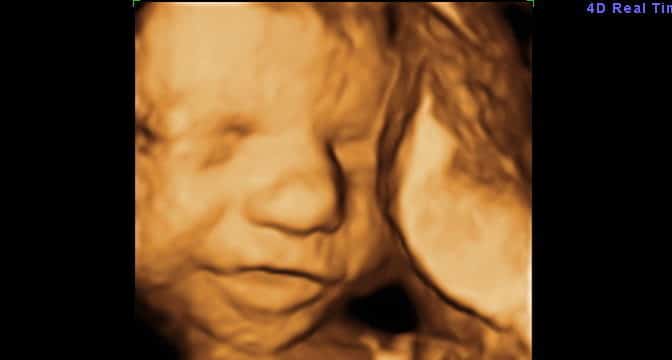

O Bebê Seu bebê está pesando cerca de 900-1000 gramas e medindo cerca de 31-32 cm de comprimento (dos pés…